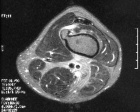

Case 10

55 year old man with left distal thigh pain for last six months to a year, it is worse with activity and relieved by rest